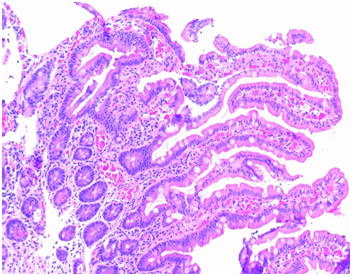

We report three patients with suspected gluten intolerance; cases 1 and 2 have negative IgA anti-TGt and IgA anti-DGP and positive IgG anti-DGP; duodenal biopsies are Marsh 3b.9 Only case 2 has positive HLA-DQ8 haplotype, case 1 was not done (Figure 1) (Table 1).

Figure 1 Pathology results in case 2. Coeliac disease. Small duodenal biopsy in case 2. Panoramic view of endoscopy duodenal biopsies with height shortening and widening of some duodenal villi. Lamina propria with lymphocites and plasmatic cells. Marsh 3B.